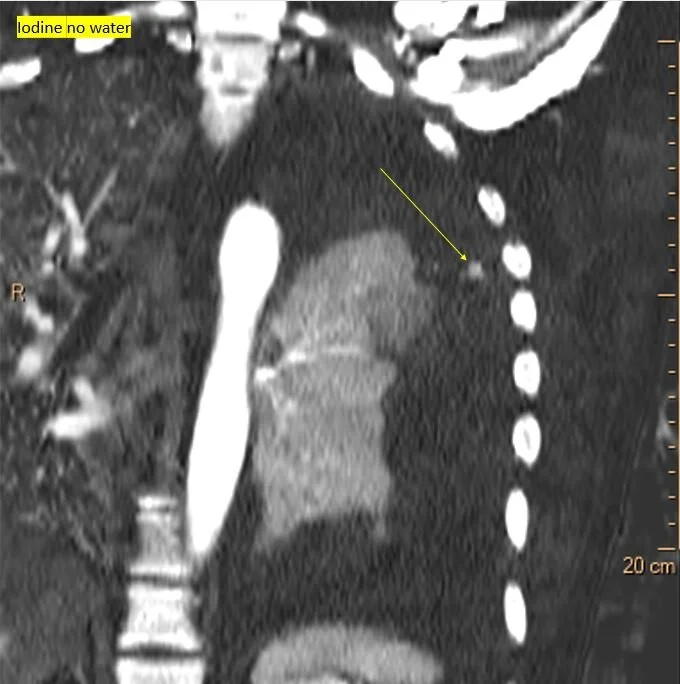

Iodine map shows focal nodule of uptake in the pleural thickening

40 keV monoE: Nicely depicts the aneurysm!